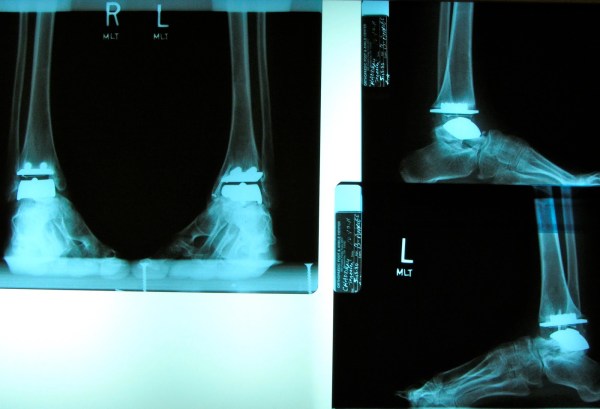

In March of 2010 I had my left ankle replaced using the (STAR) method. I had my right one done 14 months later. My surgeon, Dr. Gregory Berlet is a leading expert in the field and had been involved in a variety of clinical trials. He is a remarkable man and a terrific doctor. My life has been forever changed because of him!